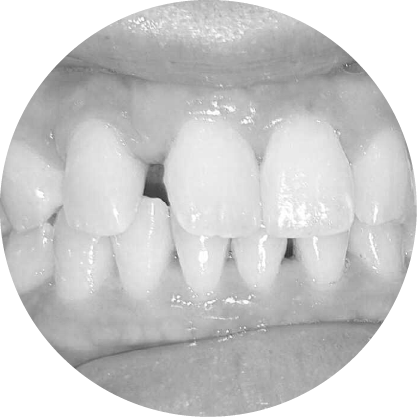

การสบฟันแบบเปิด (Anterior Open Bite)

การปิดช่องว่างระหว่างฟัน เพื่อการสบฟันที่มีประสิทธิภาพ

การสบฟันแบบเปิด โดยเฉพาะการสบฟันแบบเปิดด้านหน้าซึ่งฟันหน้าไม่สัมผัสกัน อาจส่งผลต่อการรับประทานอาหารและการพูด การแก้ไขทางทันตกรรมจัดฟัน จะเน้นที่การจัดฟันให้เรียงตัวกันใหม่เพื่อปิดช่องว่างและฟื้นฟูกลไกการสบฟัน ที่เหมาะสม

ตัวอย่างในชีวิตจริง